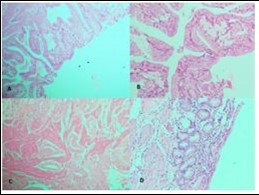

Figure 1.Photomicrographs showing A, Rokitansky agghste sinuses characteristic of chronic cholecystitis; B, Acute on Chronic Cholecystitis; C, Follicular Cholecystitis; D, Foamy macrophages admixed with mcaumulaig inflammatory infiltrate seen in Zbanikagmapincitma Cholecystitis (H&E)